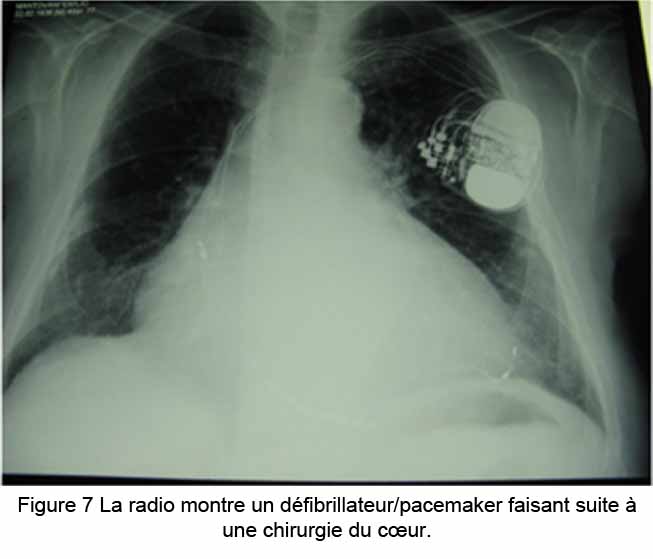

À partir de là, un système de vaisseaux et de ganglions (nœuds) lymphatiques transportent le LCR au plancher de la bouche et au cou, s’engageant finalement dans le système veineux.[105,107] Quand le cœur souffre d’un trouble du rythme, les patients sont traités avec des drogues pour réguler le rythme ou l’arythmie, ou ils sont traités chirurgicalement, par exemple avec des ablations, ou avec le placement temporaire/définitif d’un pace maker et de défibrillateurs (défibrillateurs cardiaques implantables) (Fig 7) [108-110]